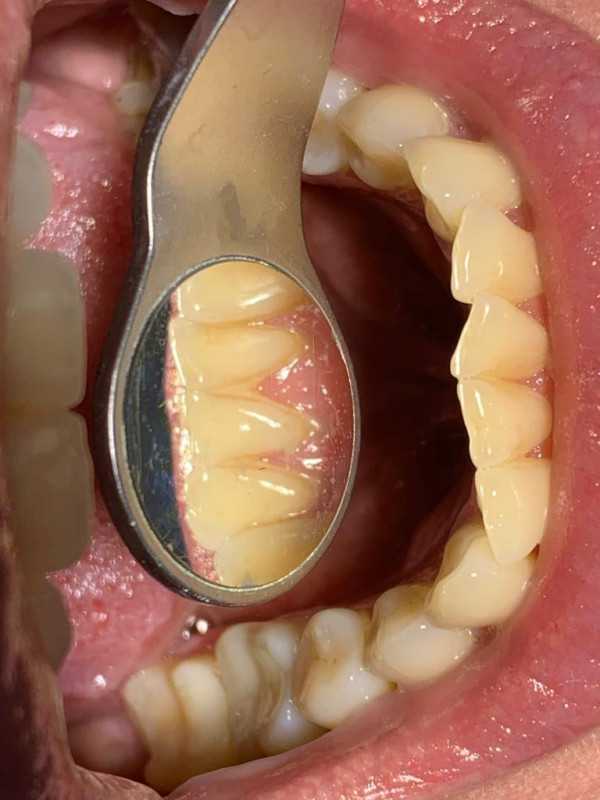

Чистка зубов Air-flow

Доктор: Пустошилова Александра Сергеевна